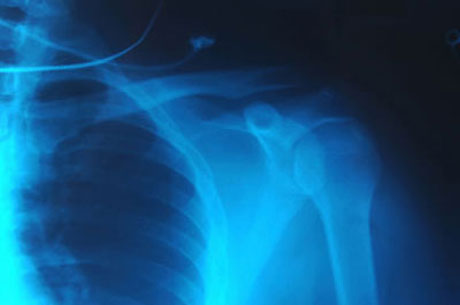

a sling

It was tied to a sling.

The best example of a 'sling' is a special device, usually made of cloth that is fastened around the neck to support an injured or broken arm. Notice the following:

- I had my arm in a sling for three weeks.

- The sling was a little uncomfortable.